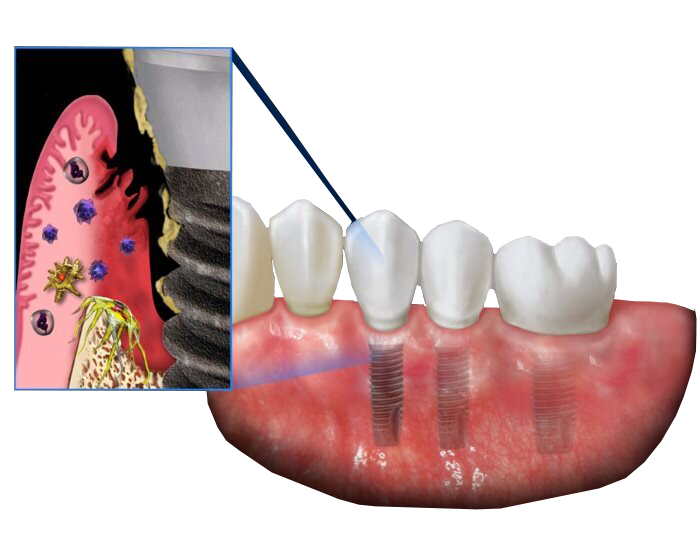

На примере постановки импланта на верхней челюсти в боковом фрагменте мы разберем частые ошибки, ведущие к развитию перииимплантита.

Критические ошибки имплантации в синусе

Герметичность соединения имплант-абатмент. Так ли это важно?

Инфекция через 3...2…1